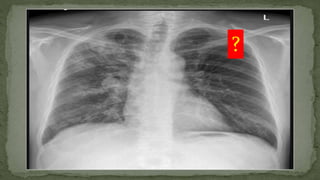

Left Pneumothorax

?

Right Pneumothorax